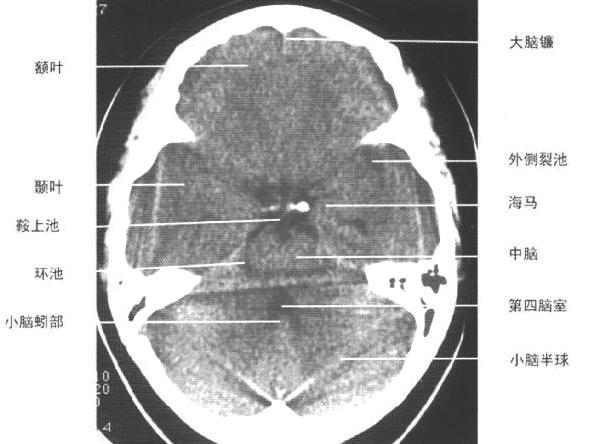

| 第三脑室下部层面

|